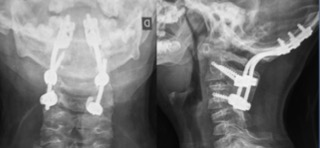

- Figura 8. Radiografías cervical AP y Lateral

- Figura 7. Radiografías Post revisión AP y Lateral